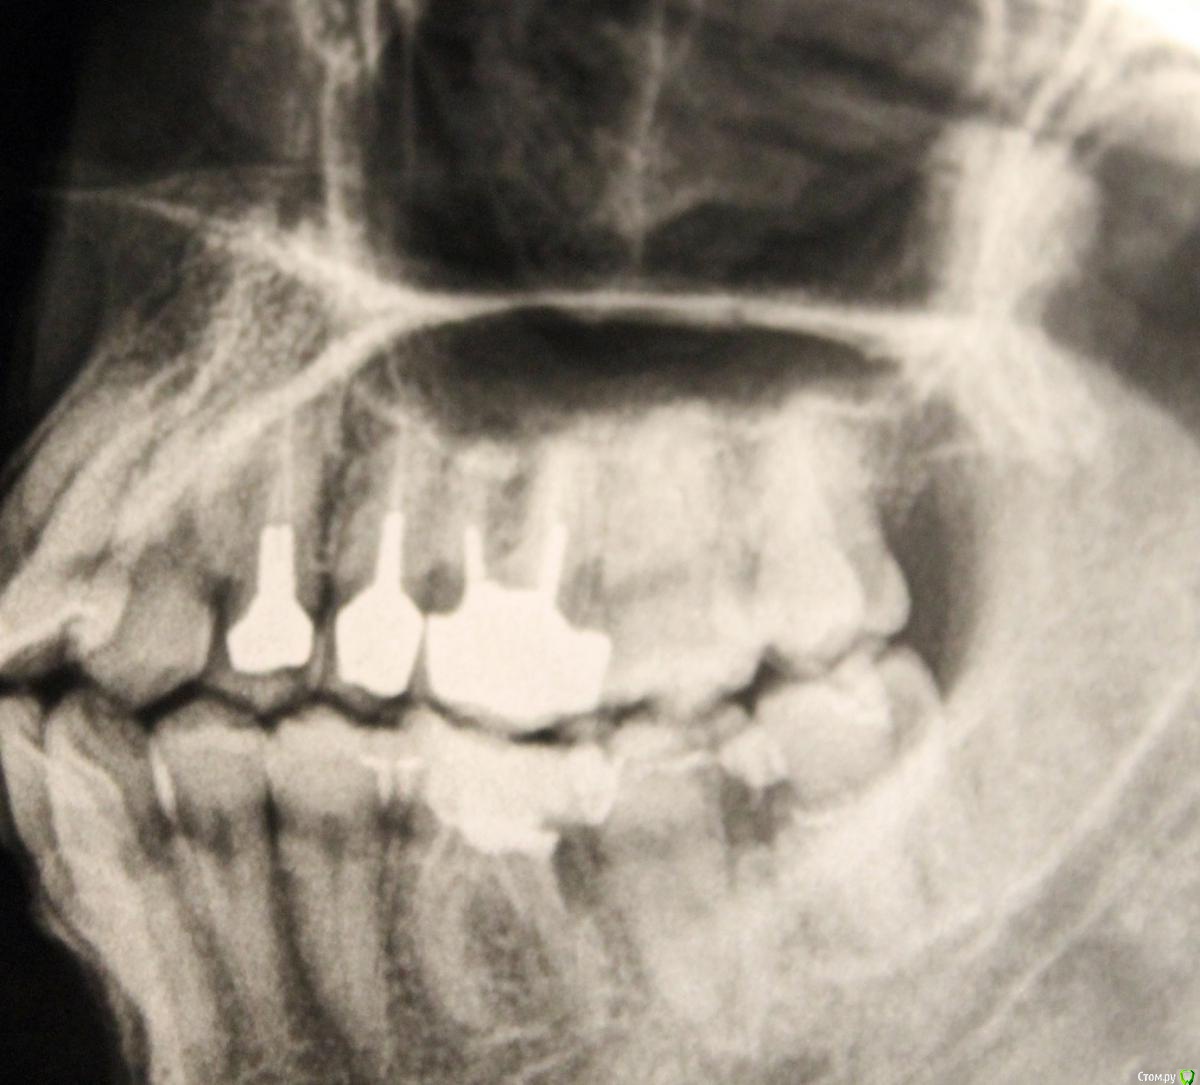

Юми Опубликовано 6 июня, 2015 Поделиться Опубликовано 6 июня, 2015 http://s017.radikal.ru/i416/1506/81/8bb1761d14c5.jpg24,25 зубы что можно сделать Ссылка на комментарий

Scrabble Опубликовано 6 июня, 2015 Поделиться Опубликовано 6 июня, 2015 (изменено) Перелечить. Хотя 24-не исключено, что треснул. Изменено 6 июня, 2015 пользователем Scrabble Ссылка на комментарий

Паращук Роман Опубликовано 6 июня, 2015 Поделиться Опубликовано 6 июня, 2015 Спасибо, врач тоже предположил что есть трещинаКТ сделаю завтра, но к врачу только во вторник попаду (а зуб 25 болит и температура(()кт трещину не покажет,если она не в палец.ПиСи 4,5,и лучше 6 переделать Ссылка на комментарий